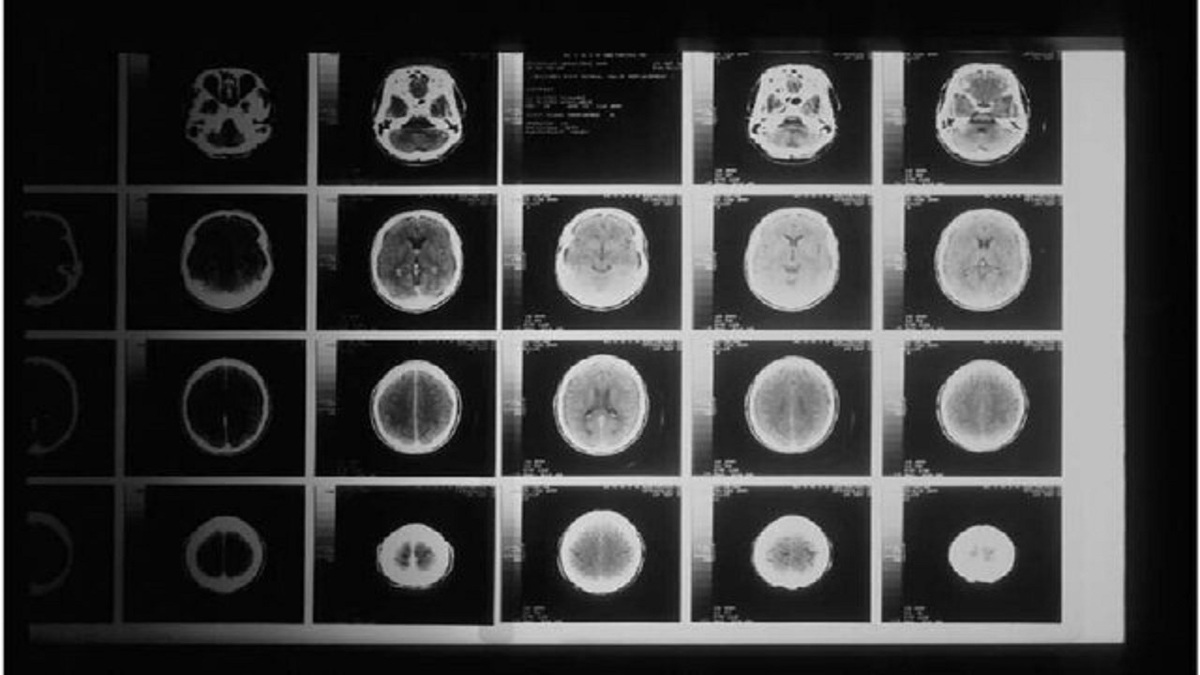

تشخیص سریع تومور مغزی در کمتر از ۲ ساعت

دانشمندان روشی فوق‌العاده سریع برای تشخیص ژنتیکی تومور‌های مغزی توسعه داده‌اند که زمان لازم برای دسته‌بندی این تومور‌ها را از شش تا هشت هفته به تنها دو ساعت کاهش می‌دهد.

دانشمندان و پزشکان روشی فوق‌العاده سریع برای تشخیص ژنتیکی تومور‌های مغزی توسعه داده‌اند. این روش که در مقاله‌ای در مجله Neuro-Oncology منتشر شده است، توسط دانشمندان دانشگاه ناتینگهام و پزشکان بیمارستان‌های دانشگاهی ناتینگهام (NUH) توسعه یافته است.

به نقل از مدیکال‌اکسپرس، در این مطالعه، محققان این روش جدید را در ۵۰ عمل جراحی تومور مغزی به کار گرفتند و توانستند تشخیص‌هایی سریع و دقیق حین عمل ارائه دهند.

این روش موفقیتی ۱۰۰ درصدی به‌دست آورد و نتایج تشخیصی را در کمتر از دو ساعت پس از جراحی، و طبقه‌بندی دقیق تومور‌ها را تنها در چند دقیقه پس از توالی‌یابی ارائه داد. همچنین قابلیت ادامه توالی‌یابی در این پلتفرم، امکان تشخیص کامل یکپارچه را در مدت ۲۴ ساعت فراهم می‌کند.